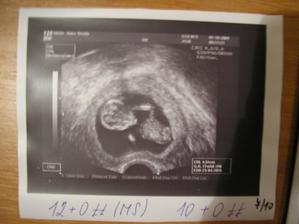

7.10. kontrola na vaginálním ultrazvuku (byl s námi i tatínek🙂 ) a testy moče (v pořádku). Odebrána krev a poslána na genetiku jakou součást NT screeningu. Konečně jsem dostala průkazku a taky 2 prenatal boxy plné milých dárečků.

15.10. Genetika - ultrazvuk opět s tatínkem. Mimísek se nechtěl otočit a pořád se válel na zádíčkách - nakonec ho pan doktor přemluvil (násilím 🙂) a otočil ho z profilu. Šíjové projasnění 1,7mm - takže v pořádku ;-D